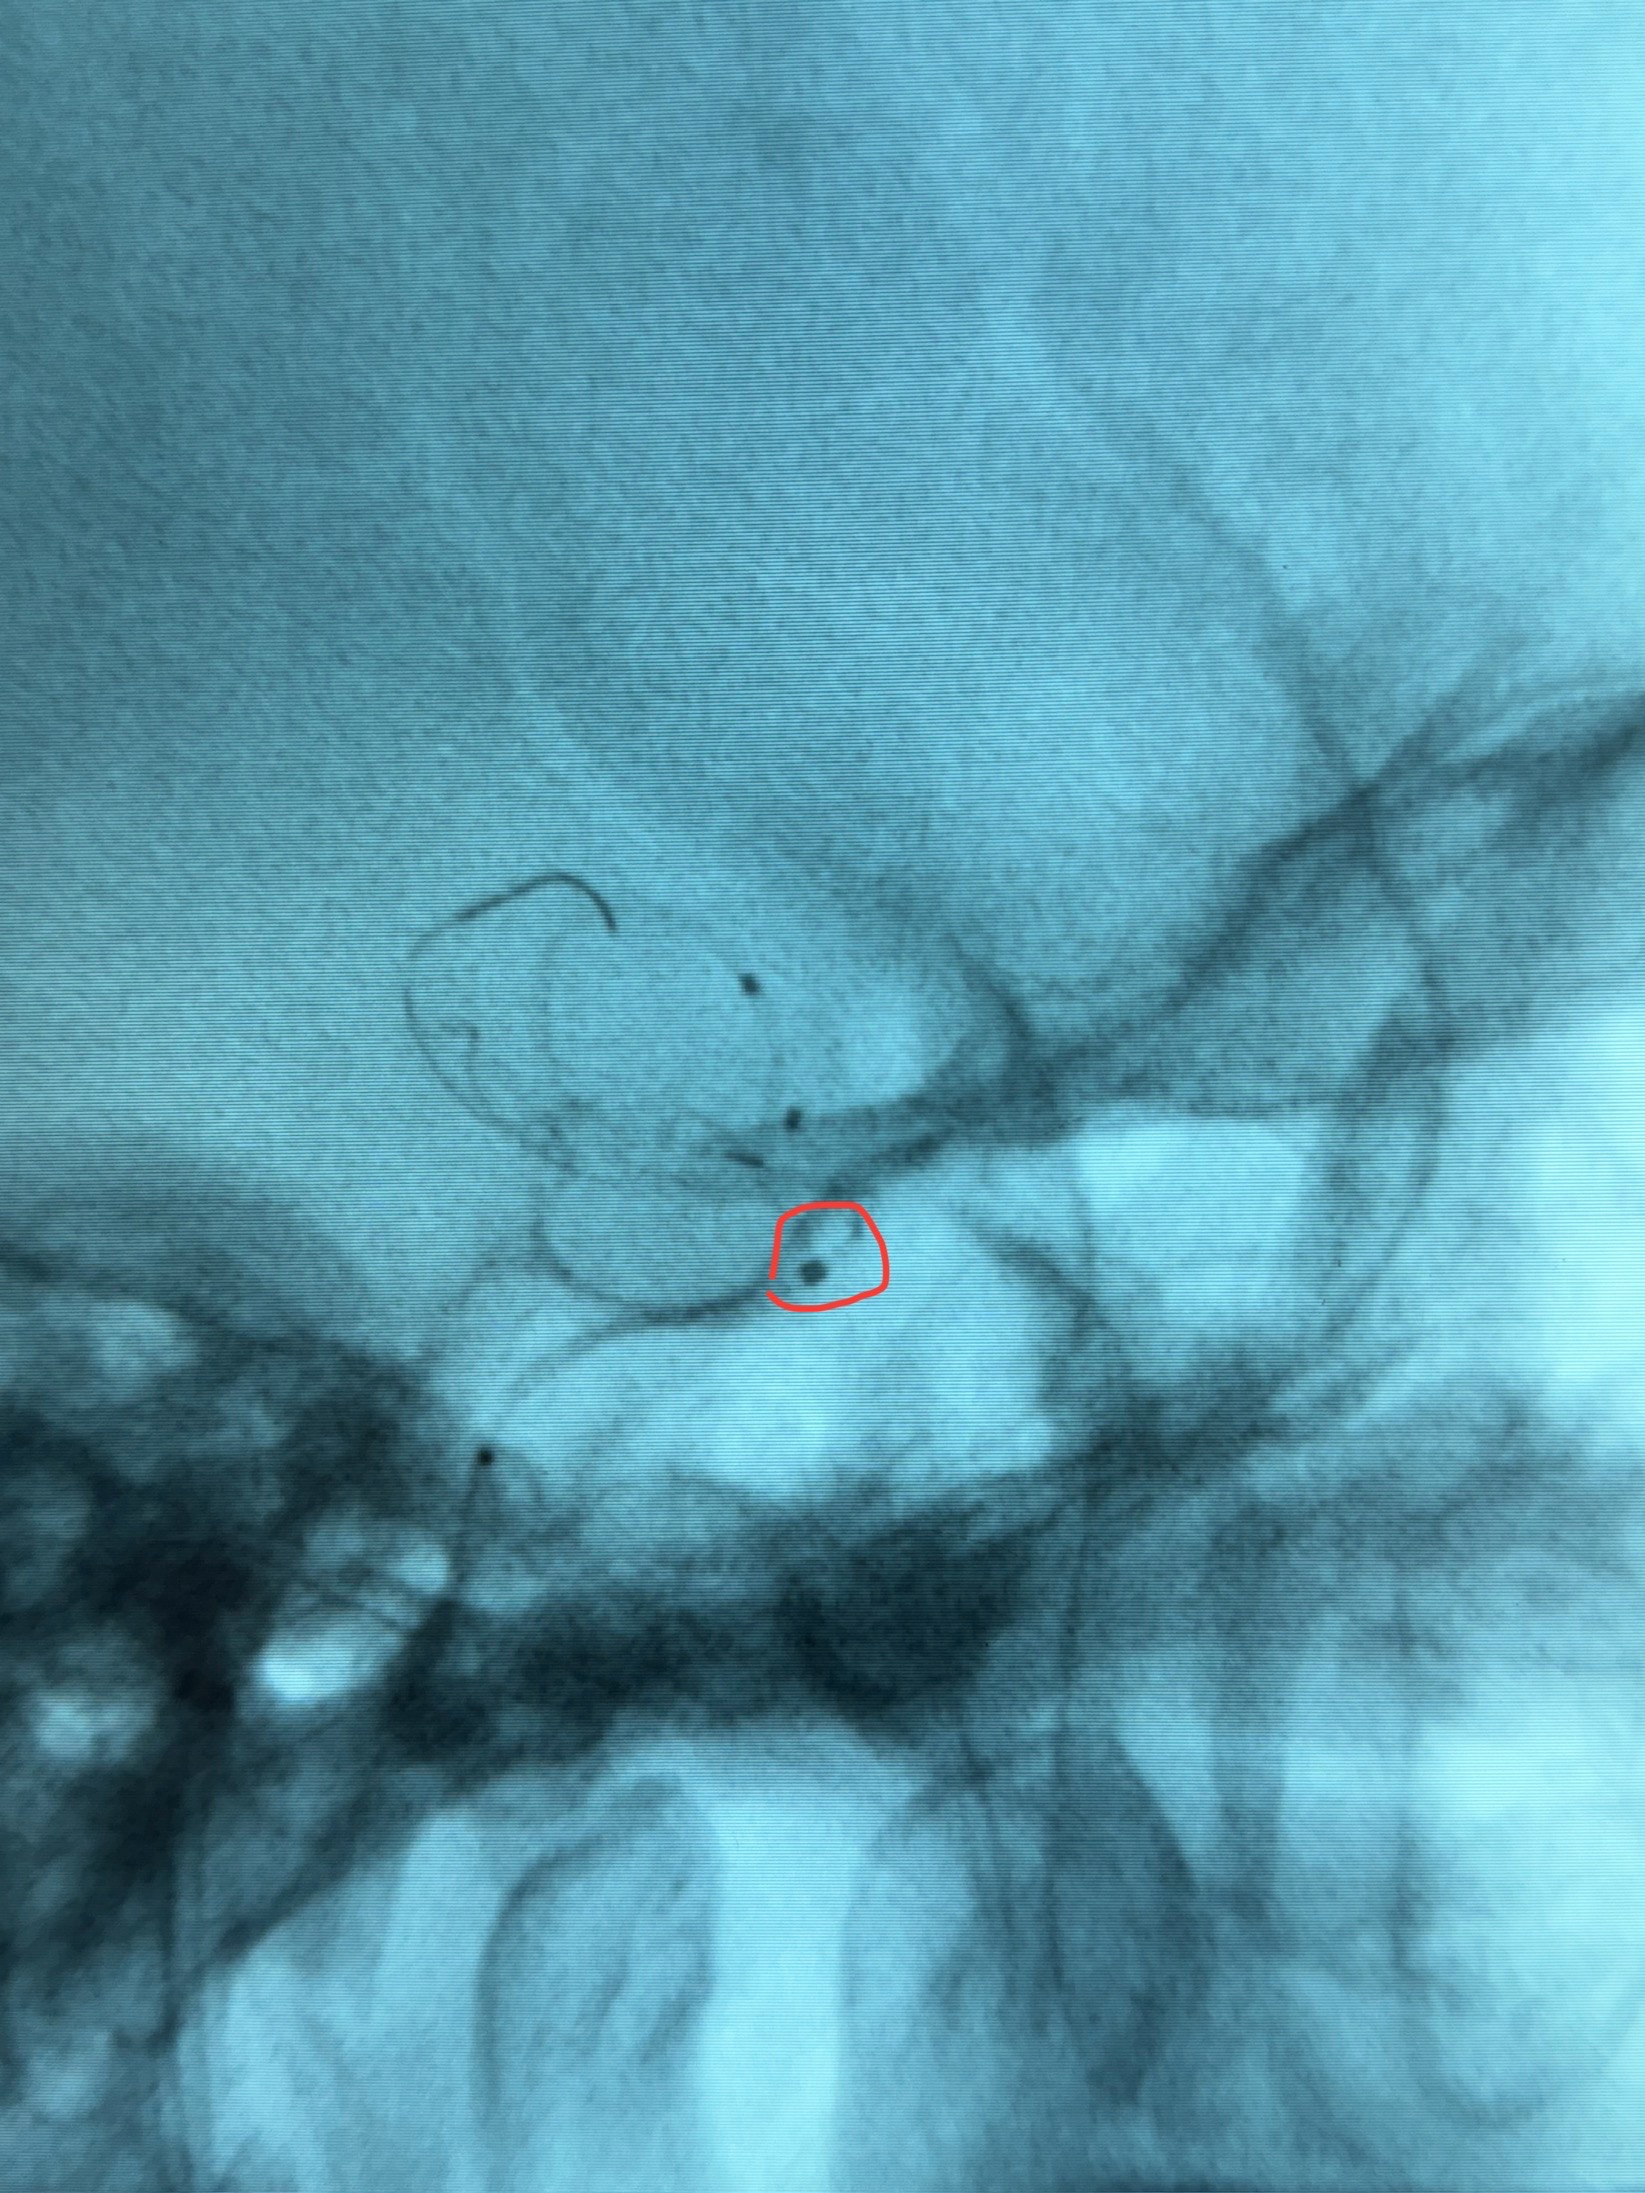

透视可见红圈部分为支架导管的头端

手推冒烟显示支架位置及展开情况,箭头为支架导管的位置